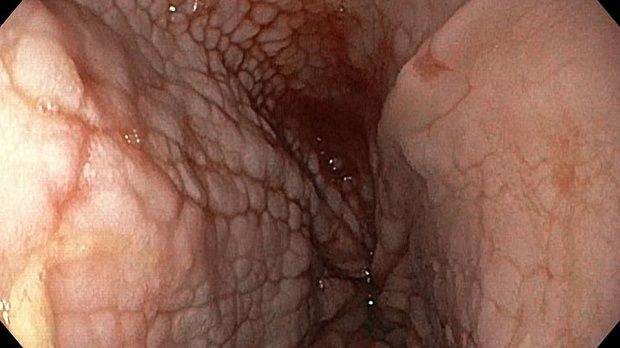

Публикации из социальных сетей: “Cobblestone esophagitis” (эзофагит со слизистой булыжной мостовой)

“Cobblestone esophagitis” (эзофагит со слизистой булыжной мостовой) - редкая эндоскопическая находка и ассоциируется с эозинофильным эзофагитом, кандидозом и пищеводом Барретта у взрослых. Он также может быть найден при тяжелом рефлюкс-эзофагите, вторичен к дистальной обструкции гастроинтестинального тракта. В нашем случае - это пациент после с 9-летним стажем бандажирования кардиального отдела желудка, признаками дуоденостаза, фундальной эрозивной гастропатией, расширением пищевода и уровнем жидкости в нем при горизонтальном положении, грыжи ПОД, эрозивно-язвенном дистальном эзофагите.. Пациент просто пришел удалить полип в прямой кишке и заодно посмотреть, что творится в желудке.... Ацетообеление+NBI+биопсия. ИПП на 3-4 мес и повтор для решения о Барретте.